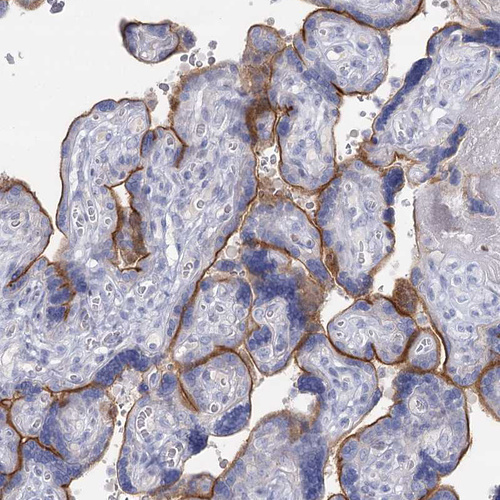

Immunohistochemical staining of human placenta shows strong positivity in plasma membrane in trophoblastic cells.